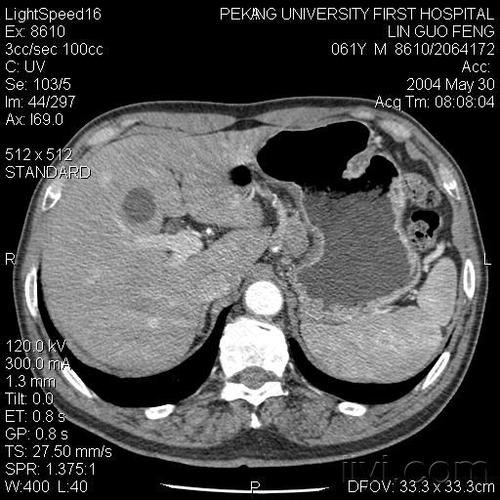

其实CT多用在检查肿瘤、骨骼系统、脑部等方面。CT是可以检查肠胃的,但是只能排查胃肠道有没有占位性病变,比如肿瘤。而且CT具有一定的放射性,对身体会有一定的伤害,要根据身体情况来选择做CT检查。